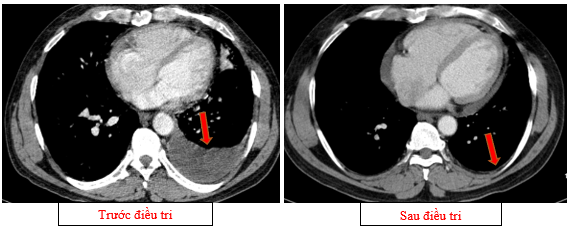

-         Chụp cắt lớp vi tính lồng ngực (08/2025): Khối rốn phổi trái ôm quanh nhánh phế quản thùy dưới trái kích thước 28x26mm, dày tổn chức kẽ vách liên tiểu thùy và nhiều nốt đặc lan tỏa khắp nhu mô, đường kính <7mm. Màng phổi trái có vài nốt đặc ngấm thuốc nốt lớn nhất kích thước 17x15mm  Khoang màng phổi trái có dịch dày 54mm. Nhiều hạch to trung thất, rốn phổi hai bên và hố thượng đòn có hoại tử trung tâm, hạch lớn nhất kích thước trục ngắn 22mm.

Hình 01: Nhiều hạch to trung thất, rốn phổi hai bên và hố thượng đòn có hoại tử trung tâm, hạch lớn nhất kích thước trục ngắn 22mm

-         Chụp cắt lớp vi tính lồng ngực (11/2025): Màng phổi vùng rốn phổi trái dày,dày tổ chức kẽ vùng ngoại vi đáy phổi hai bên. Màng phổi trái có vài nốt đặc ngấm thuốc nốt lớn nhất kích thước 17x15mm. Khoang màng phổi hai bên không có dịch – khí (Tổn thương giảm đáng kể so với phim chụp 08/2025). Trung thất, rốn phổi hai bên, hố thượng đòn trái có vài hạch, hạch lớn nhất kích thước 12x6mm. Vài nốt đặc xương rải rác thân đốt sống, các cung xương sườn hai bên.

Hình 08: Khối u đáp ứng gần hoàn toàn, chỉ còn tổn thương dạng kính mờ, các tổn thương dày tổ chức kẽ vách liên tiểu thuỳ, nốt đặc rải rác 2 trường phổi cũng gần như biến mất.

Hình 09: Không còn tổn thương tràn dịch màng phổi trái trên phim chụp

+      Khối u rốn phổi trái thoái triển gần hoàn toàn, các tổn thương dày tổ chức kẽ vách liên thùy và nốt đặc rải rác hai trường phổi phổi giảm rõ

+      Không còn tràn dịch màng phổi.